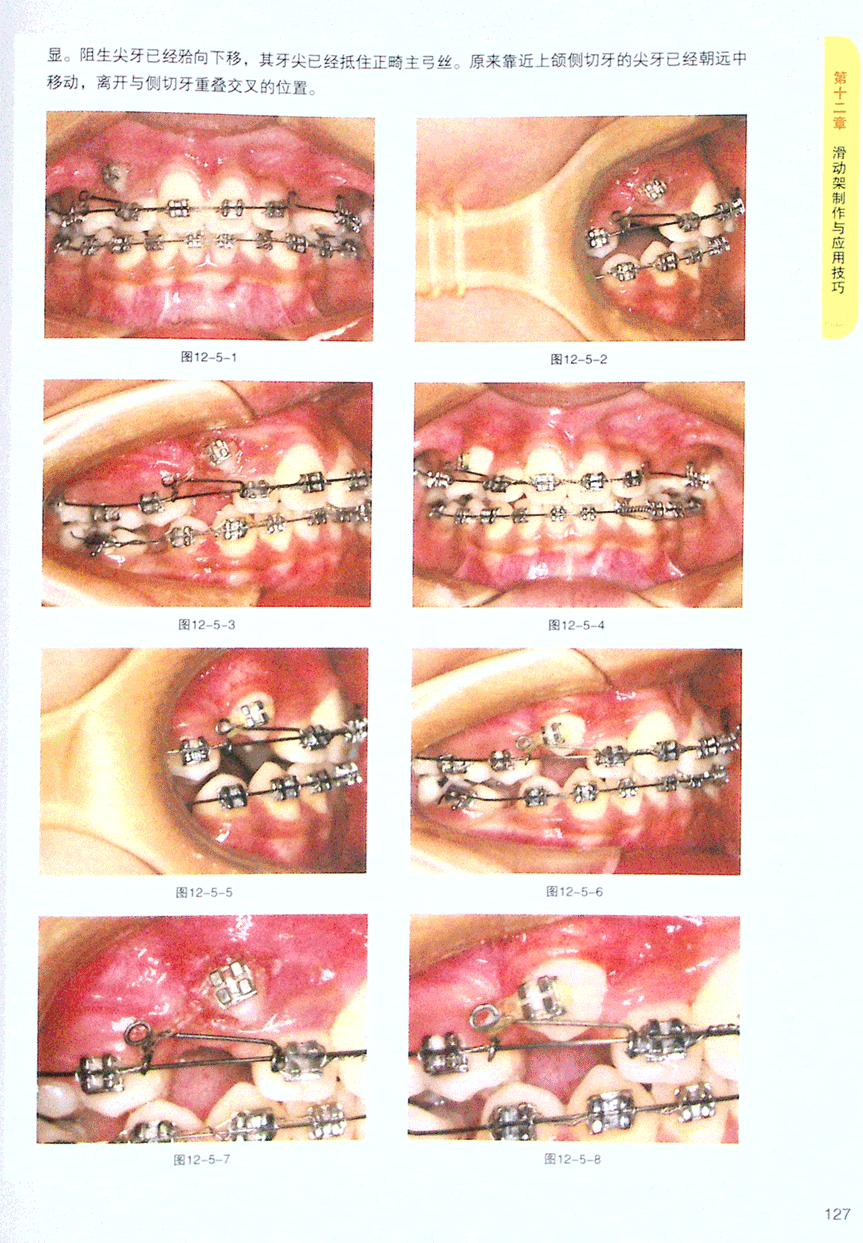

第五节 阻生上尖牙导萌倒放滑动架牵引技巧